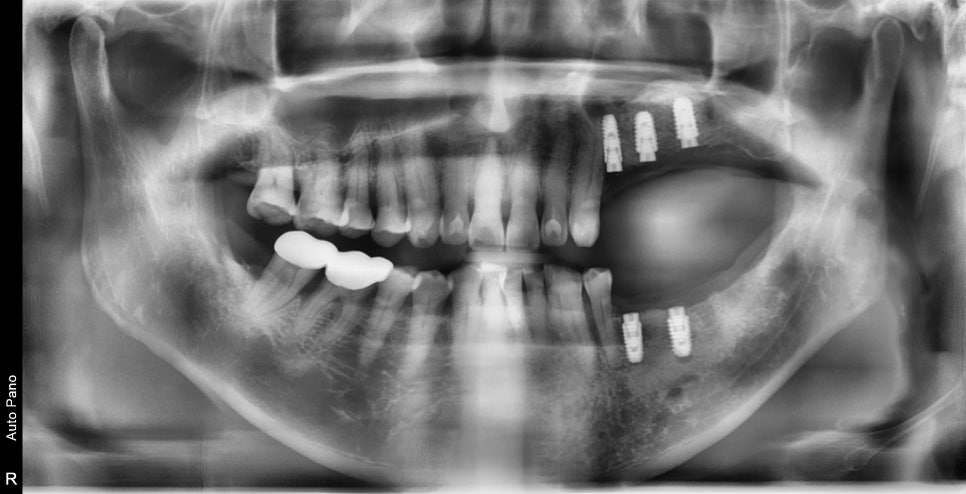

23.12.15 — 아래 임플란트 식립 / 24.09.04 — 치료 완료

위 회복 확인 후 아래를 순차적으로 진행했습니다. 빠르게 끝내는 것보다 각 단계마다 회복을 확인하며 진행하는 방식을 택했습니다. 총 치료기간은 약 1년 4개월이었습니다.